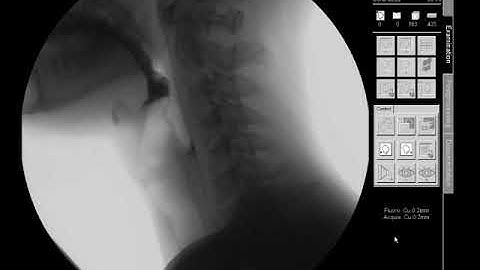

Swallow Study - Solid Texture/Cracker - Modified Barium Swallow Study (MBSS) Lateral View HD